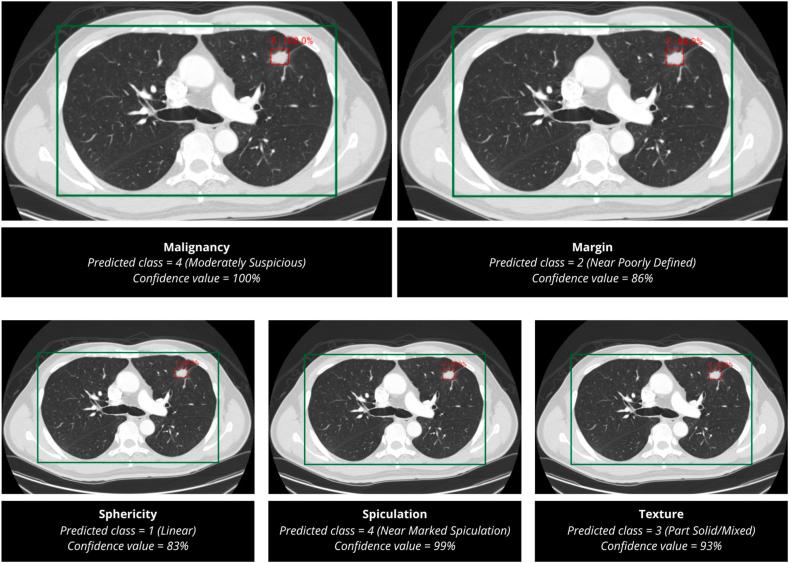

AIPS-N achieved an average AP50 of 70.19% in detecting the location of nodules within the lung region of interest during validation and predicted the score of five lung nodule properties. The AIPS-M machine learning (ML) and deep learning (DL) models achieved AUCs ranging from 0.587 to 0.910.

在验证期间,AIPS-N在检测感兴趣肺区域内结节位置时的平均AP50为70.19%,并预测了五种肺结节属性的评分。AIPS-M机器学习(ML)和深度学习(DL)模型的AUC范围为0.587至0.910。